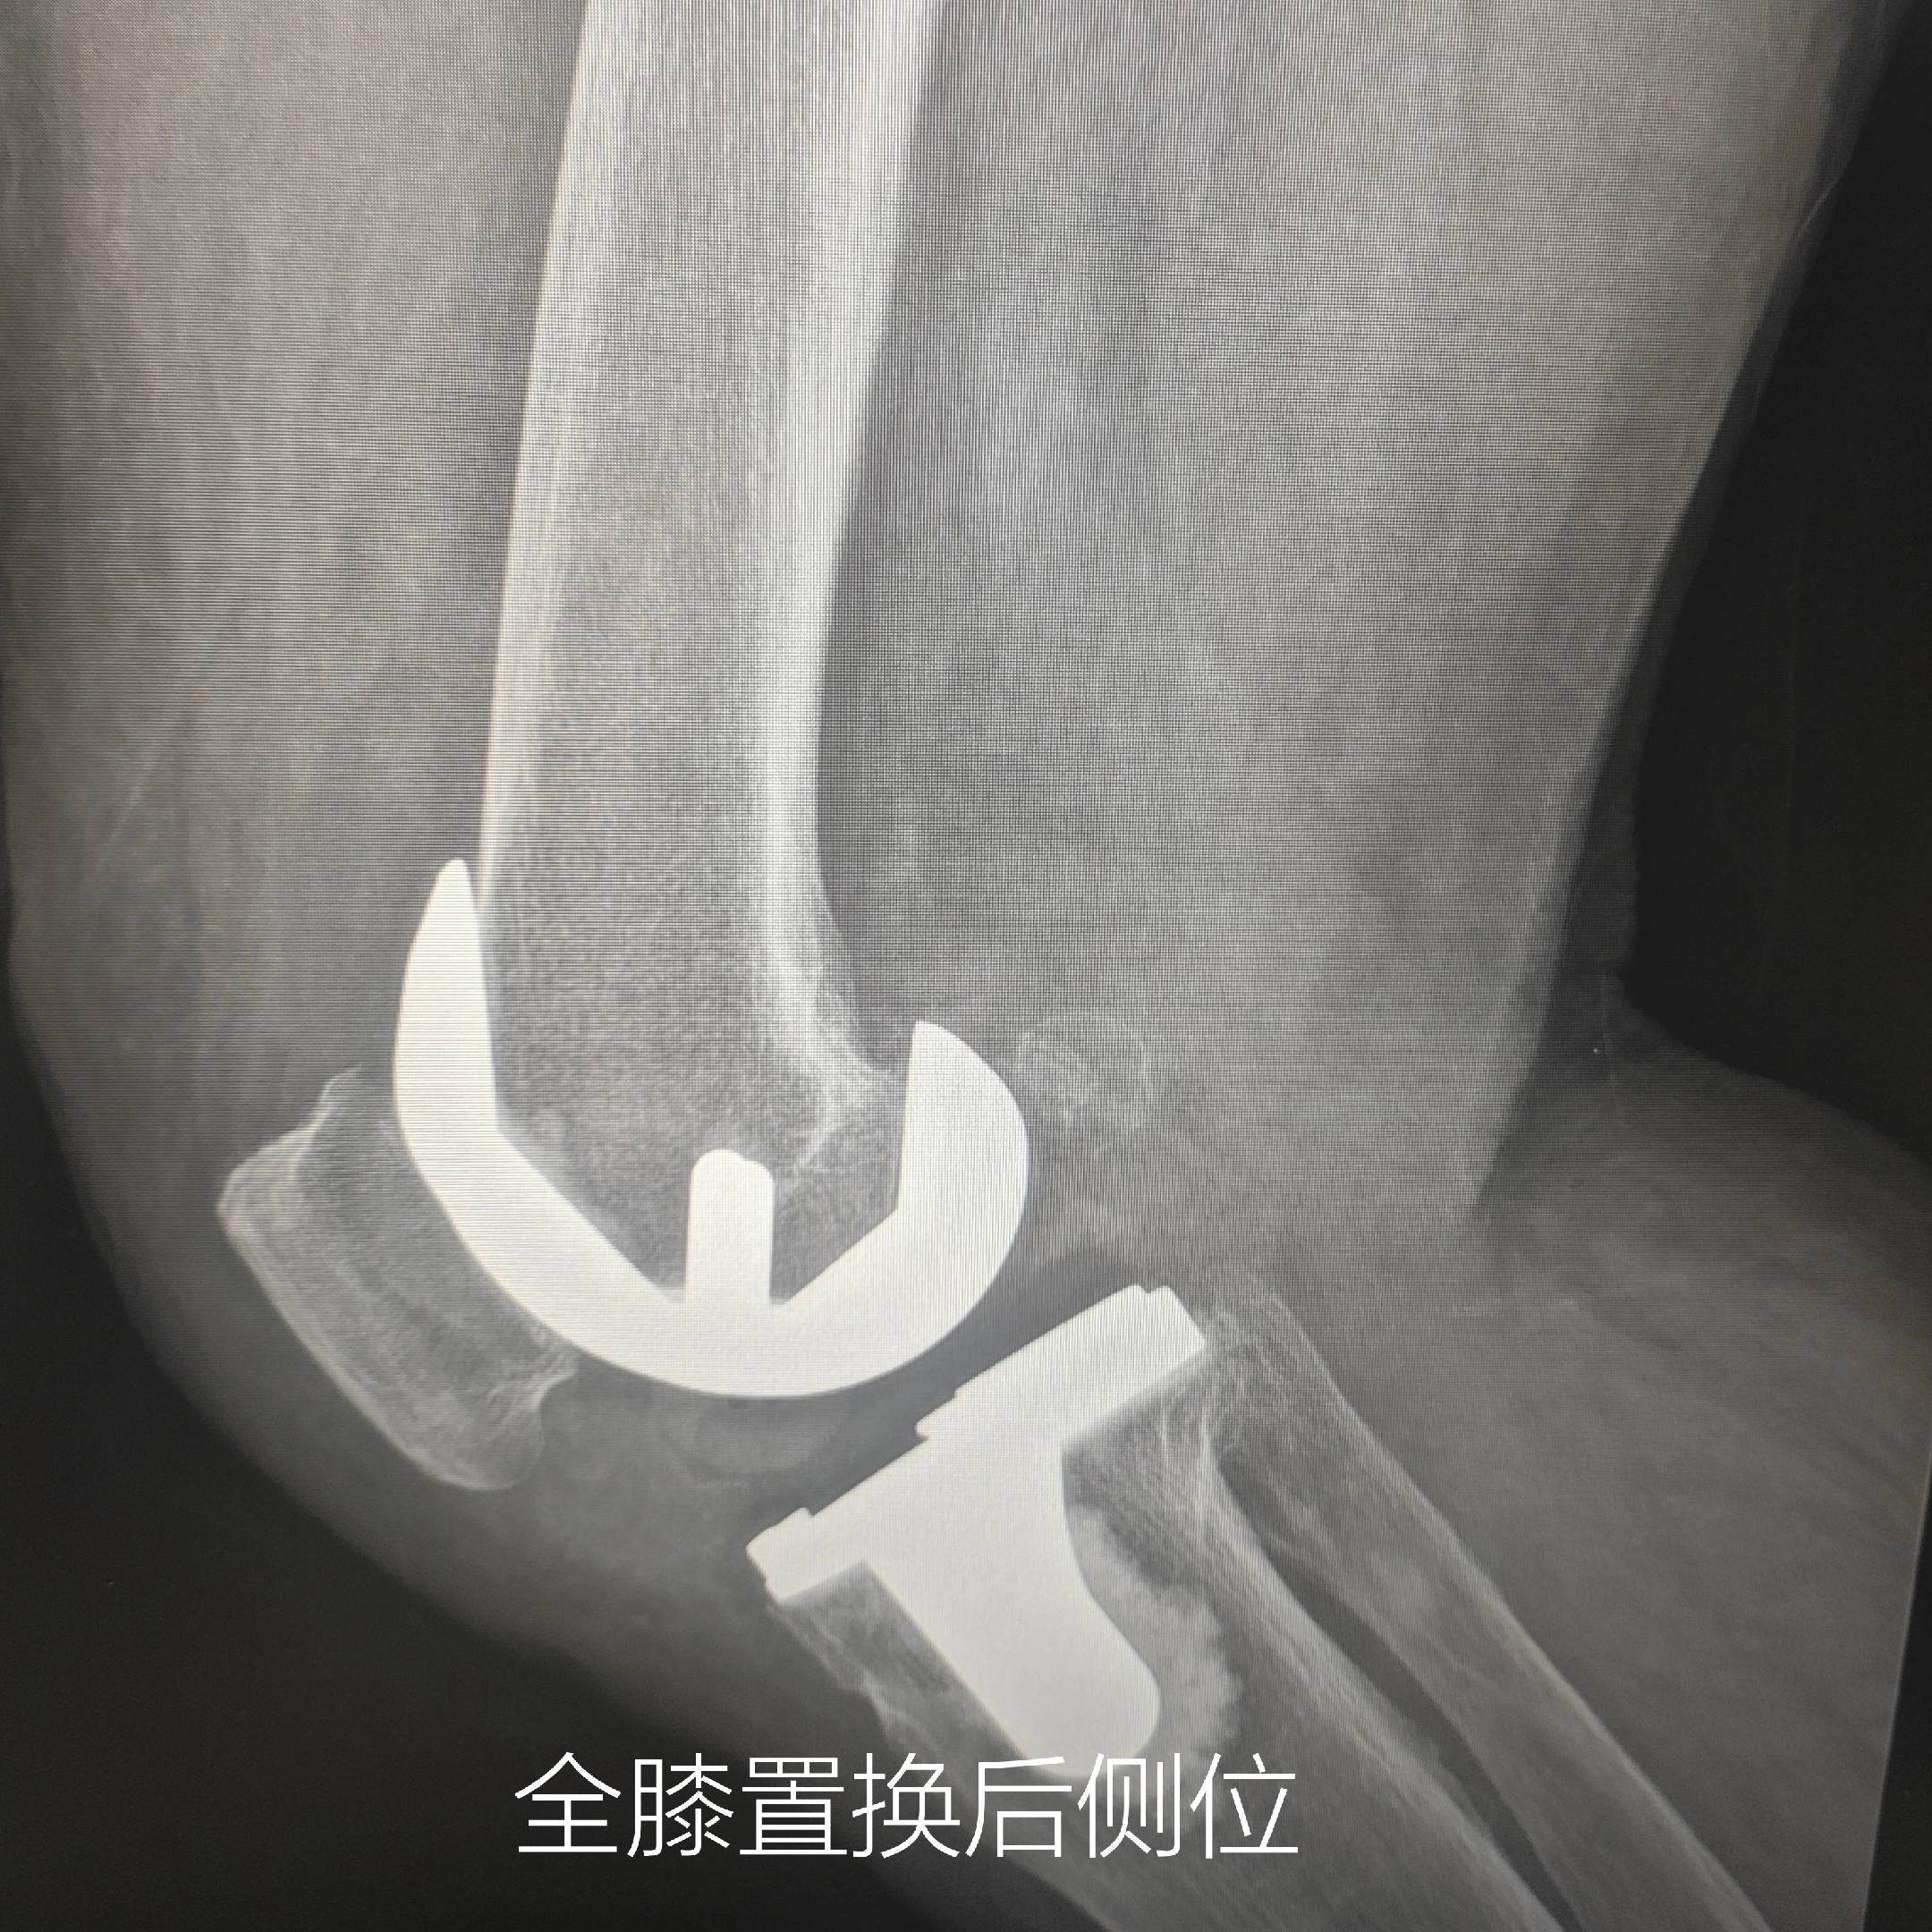

膝关节痛。